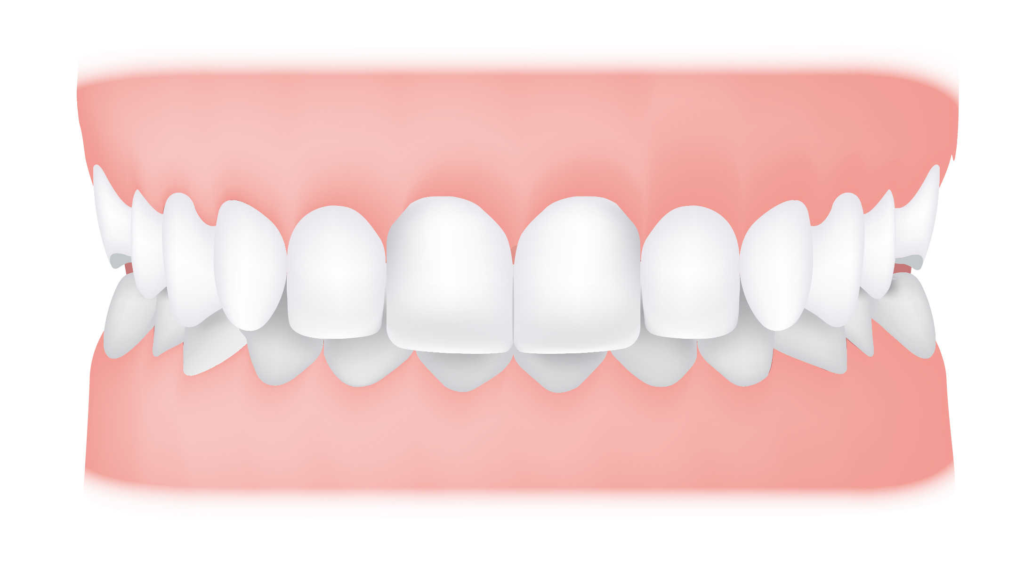

An overbite is the vertical overlap between the upper and lower front teeth when the back molars bite together. Overbites of up to 2 millimeters are considered normal and ideal. However, when there is an excessive overlap exceeding 3-4 mm, it is known as a deep bite.

Difference Between Overbite and Overjet

An overbite is often mixed up with overjet or underbite as they tend to occur together. As a general guide, an overbite is when there is a vertical overlap between the upper front teeth that cover the lower teeth from top down. An overjet is however a horizontal overlap whereby the upper front teeth protrude out and over the lower front teeth.